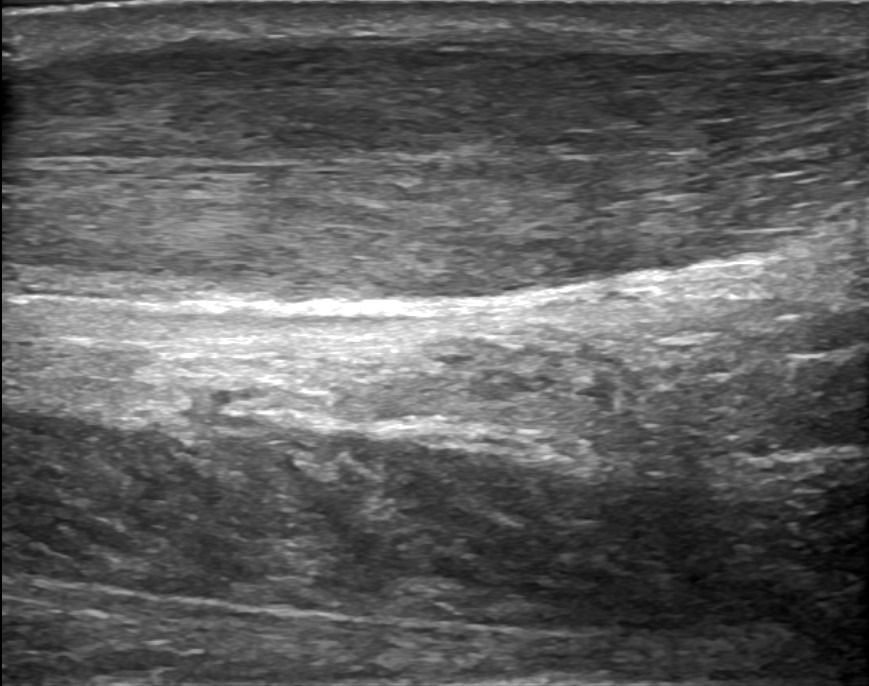

Foot Tendons

Foot Ultrasound allows the diagnosis of tendonitis, tenosynovitis, and rupture in the following tendons:

- Achilles Tendon

- Peroneal Tendons

- Flexor Tendons

- Extensor Tendons